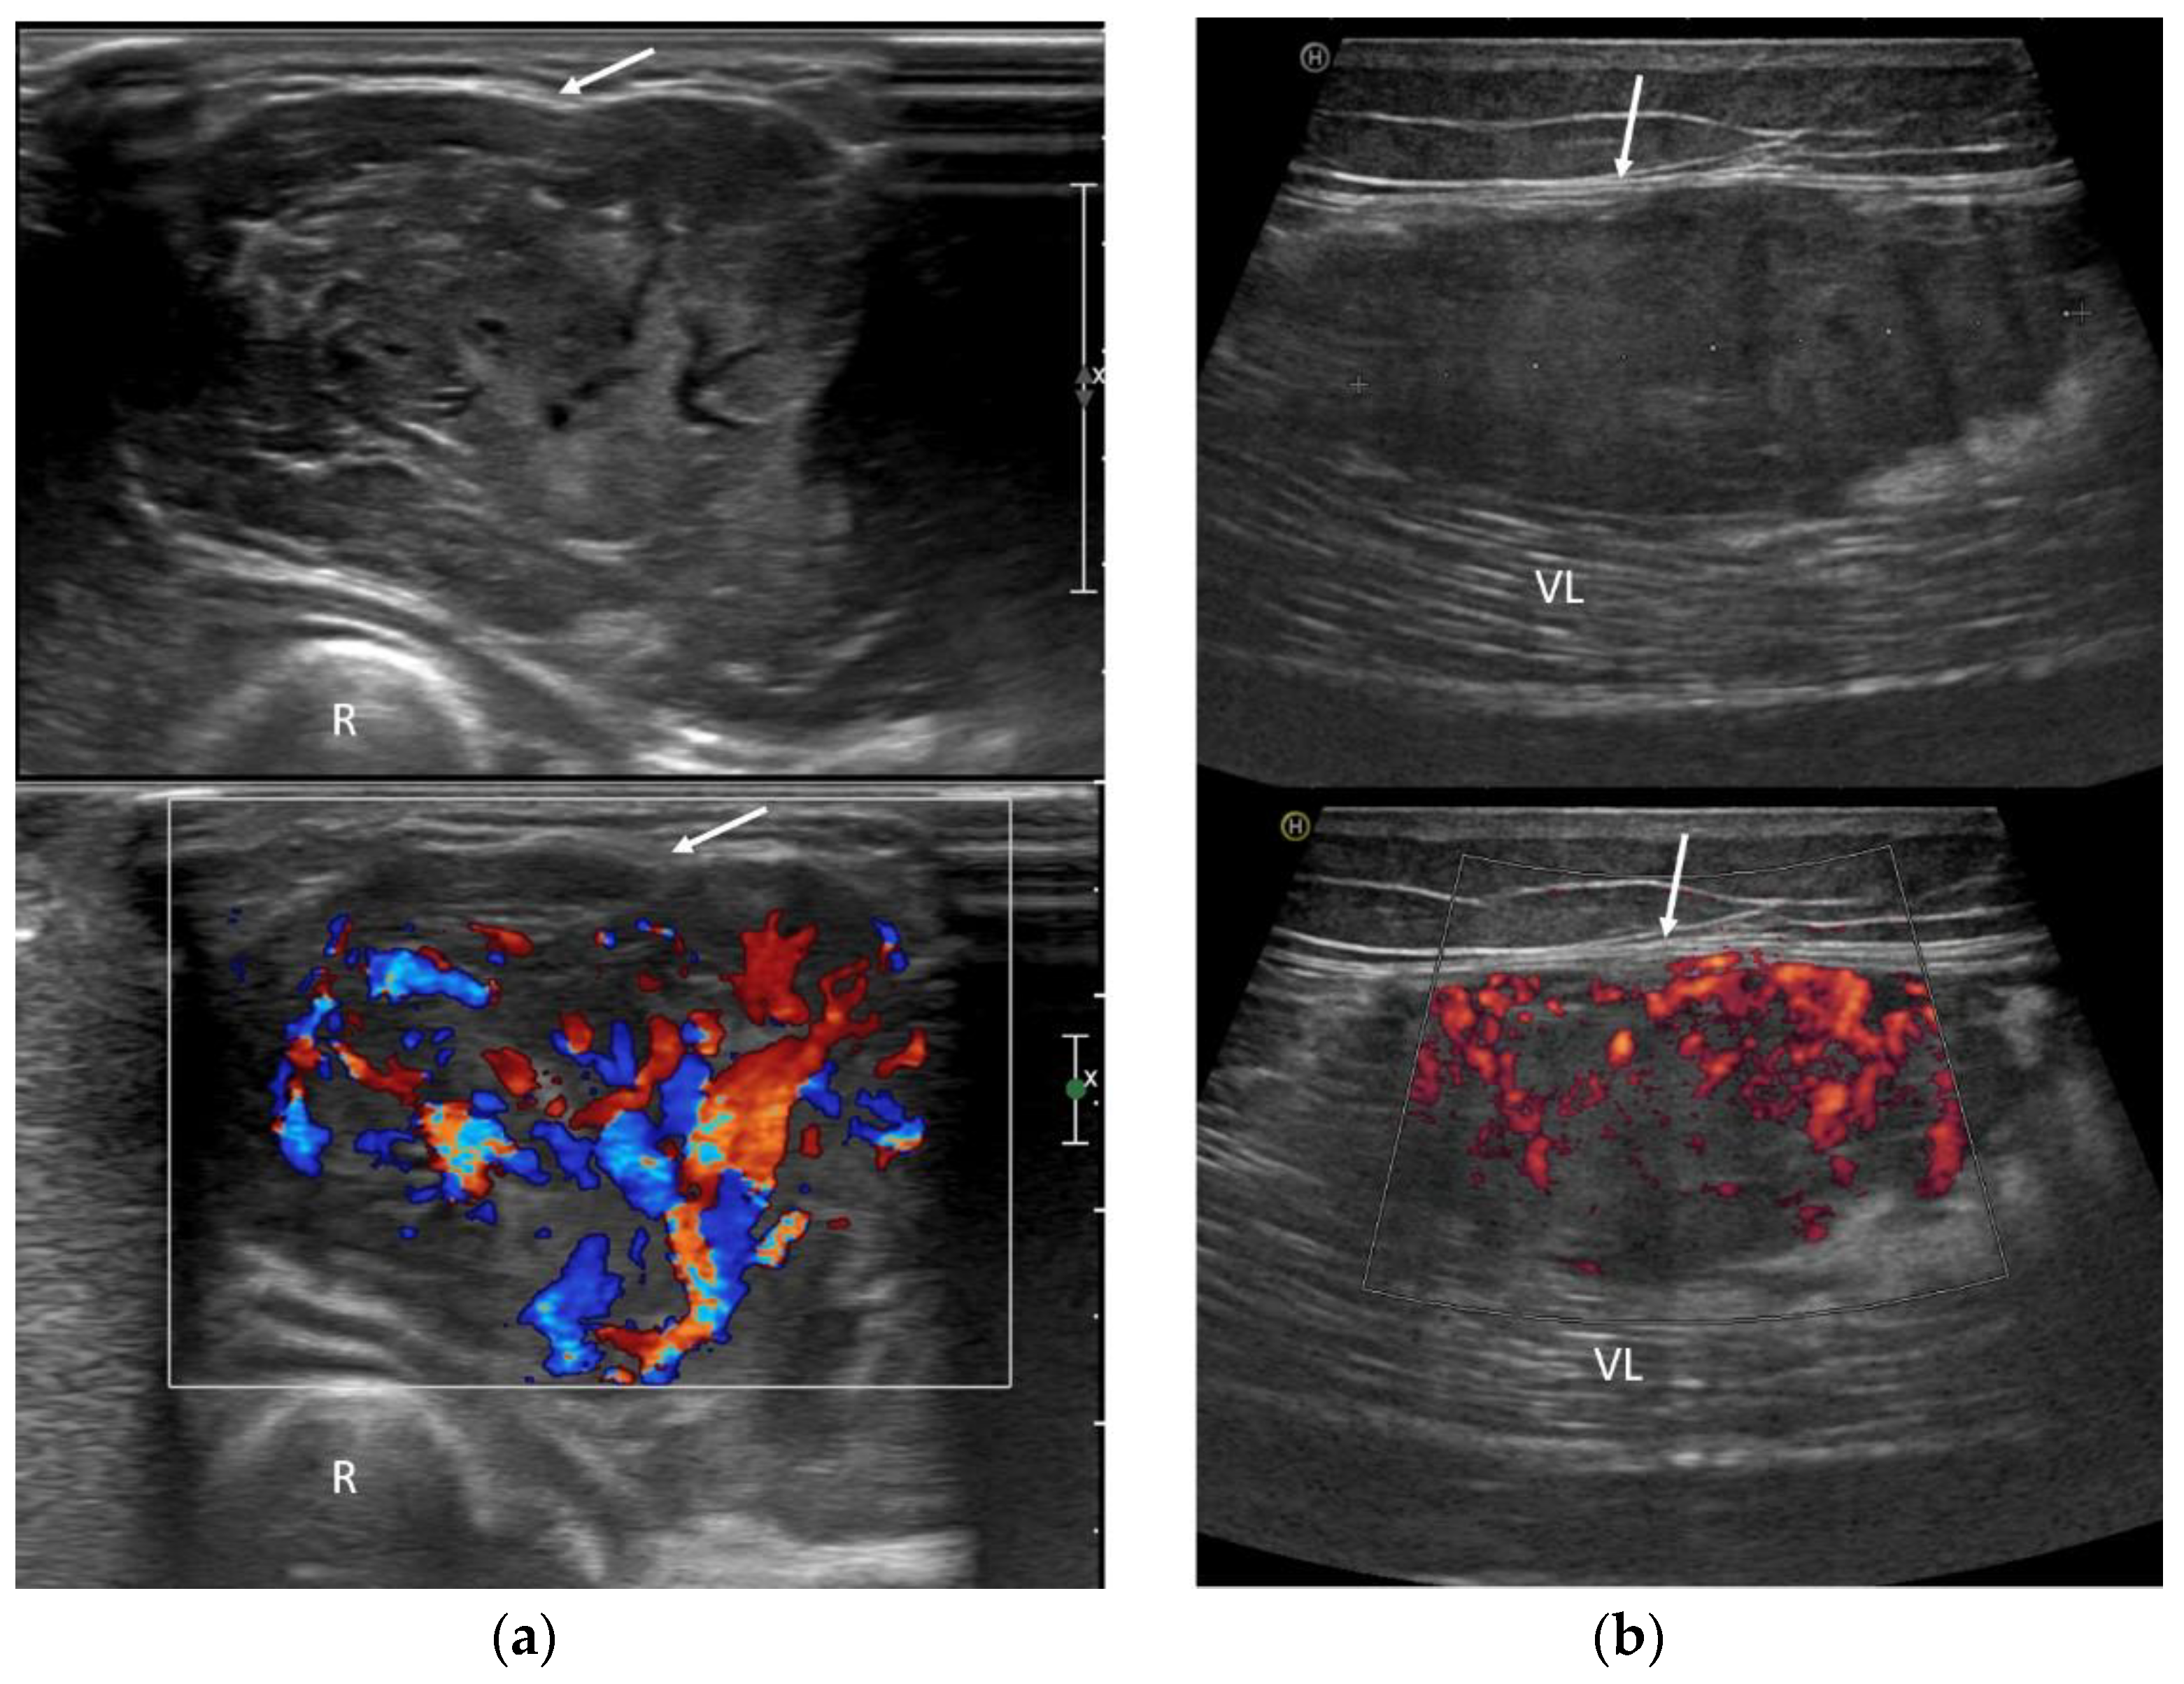

3.3. Ultrasound Features

- Inhomogeneous, mainly hypoechoic US pattern with strong internal vascularization at Color-Doppler evaluation